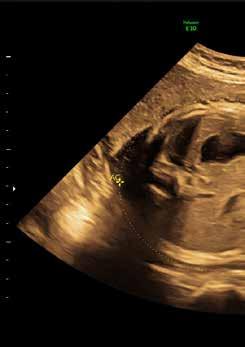

Wie geht's dir, Baby?

Ultraschlall: Für werdene Eltern sind sie Bilder beruhigend, für Mediziner eine umfassende Informationsquelle.

Es sind nur unscharfe, verwaschene Bilder in Schwarz und Weiß. Was Medizinerinnen und Mediziner allerdings darauf erkennen können, ist erstaunlich. Ultraschalluntersuchungen sind während der Schwangerschaft eine der wichtigsten Methoden, um sicherzustellen, dass es dem ungeborenen Kind gut geht.

„Grundsätzlich können wir mit Hilfe von Ultraschall prüfen, ob das Kind im Mutterleib adäquat wächst und wie sich die Organsysteme entwickeln“, sagt Prof. Dr. Christoph Mundhenke, Direktor der Klinik für Gynäkologie und Geburtshilfe an der Klinikum Bayreuth GmbH. „Für werdende Eltern ist es beruhigend, zu wissen, dass es ihrem Kind gut geht. Und in den wenigen Fällen, in denen es anders ist, ist das Ergebnis der Untersuchung nicht minder wichtig“, sagt Mundhenke. Denn dann können Eltern und Ärzte reagieren.

Die Blutversorgung der Plazenta

Dafür gibt es ein spezielles Ultraschallverfahren, dass den Blutstrom und den Fließwiderstand sichtbar macht. Beides entscheidet darüber, ob das Kind gut versorgt wird. Sollte dies nicht der Fall sein, gibt es Handlungsmöglichkeiten.

„Bis zur 34. Schwangerschaftswoche geben wir Müttern zweimal innerhalb von 48 Stunden ein

Glucocorticoid“, sagt der Klinikdirektor. Damit wird die Organreife der Lunge des ungeborenen Kindes angeschoben – eine Voraussetzung, um eine eventuelle Geburtseinleitung oder einen Kaiserschnitt in Erwägung ziehen zu können.

Die Entwicklung des Organsystems

Sind Magen- und Harnblase gefüllt? Das lässt sich im Ultraschall gut feststellen und es liefert weitere gute Erkenntnisse. Enthalten sie Flüssigkeit, ist zum Beispiel die Speiseröhre angelegt. Auch das Gehirn lässt sich mit diesem Verfahren sichtbar machen. Wenn Flüssigkeitseinlagerungen Druck ausüben und das gesunde Gewebe beeinträchtigen, hat nicht nur das Team der Geburtsklinik die Bilder auf dem Tisch. „Dann ziehen wir Neurologen hinzu und entwickeln interdisziplinär einen Vorschlag zum weiteren Vorgehen, den wir dann mit den Eltern besprechen.“ Das Spektrum reicht dabei von Beobachten und Abwarten bis hin zu einer Verlegung der Schwangeren in ein hochspezialisiertes Zentrum. Auch Fehlbildungen am Herzen lassen sich erkennen – viele davon müssen nicht operiert werden.

Sicherheit für Mutter und Kind

„Das alles dient der Sicherheit von Mutter und Kind“, sagt Mundhenke. Und dass im Ultraschall ein Befund sichtbar wird, der Anlass zur Sorge gibt, geschieht äußerst selten. Der Kontakt zwischen der Schwangeren und ihrer Geburtsklinik wird zumeist im letzten Drittel der Schwangerschaft intensiver. Schwere Fehlbildungen fallen bereits in früheren Phasen auf. Sollte es dennoch einmal zu einer solch schwierigen Situation kommen, gibt es dann Beistand für das Paar, vielleicht sogar bei der Entscheidung für

Ultraschall – wie geht das eigentlich?

Wenn das Ultraschallgerät eingeschaltet wird, sendet der Schallkopf – ähnlich wie ein Lautsprecher – für das menschliche Ohr nicht hörbare Schallwellen aus. Wenn der Schallkopf auf die Haut gesetzt wird, wandern die Ultraschallwellen in den Körper. Von dort werden sie von den Geweben und Organen wie ein Echo zurückgeworfen (reflektiert).

Verschiedene Gewebe reflektieren Ultraschallwellen unterschiedlich stark. Aus diesen Echos leitet ein Computer die Lage, Form und Struktur der Organe ab. Das wird auf dem angeschlossenen Monitor als Ultraschallbild sichtbar gemacht. Untersuchungsbefunde und einzelne Bilder können abgespeichert und ausgedruckt werden.

Bestimmte Ultraschallgeräte können auch die Richtung und Geschwindigkeit bestimmen, mit der das Blut durch die Blutgefäße oder das Herz strömt. Dies wird Doppler-Untersuchung genannt.

ˆ Blick in den Bauch: Regelmäßige Ultraschalluntersuchungen gehören in der Schwangerschaft dazu.